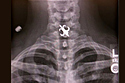

Saints Fan Swallows Earring

A Saints fan left her favorite fleur-de-lis earring next to her medication on her bedside and swallowed it along with the pills.